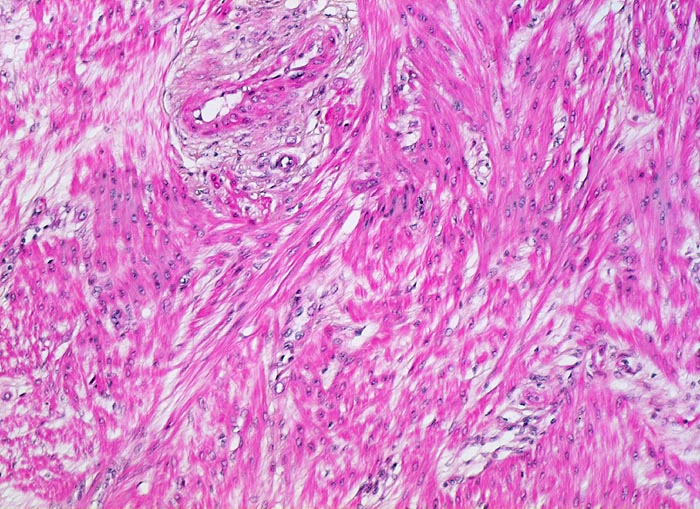

Ursache ist eine defiziente Dezidualisierung mit nachfolgender Verankerung der Plazentarzotten in der Muskulatur des Myometriums. Normalerweise trennt sich die Plazenta durch die Nitabuch Fibrinschicht, innerhalb der Dezidua basalis durch Scherkräfte zwischen der kontraktilen Muskulatur und der rigiden, nicht-kontraktilen Plazenta. Abtrennung innerhalb der Dezidua im Bereich fragiler Deziduazellen. Ist die Dezidua nicht angelegt, ergibt sich keine Trennschicht und fehlt somit die Abtrennbarkeit der Plazenta. Die Zone der Haftung kann klein sein, sodass die Unvollständigkeit der Plazenta zunächst nicht bemerkt wird. Die Plazenta accreta stellt ein charakteristisches Beispiel einer mangelhaften Dezidualisierung des Endometriums dar und zeigt beispielhaft die Bedeutung endometrialer Dezidualisierung zur Kontrolle der Trophoblastinvasion. Gleichermassen handelt es sich bei einer Tubengravidität in nicht-dezidualiserter Tuba uterina immer auch um eine Plazenta accreta und schliesslich Plazenta percreta mit Tubarruptur! Die Tubarruptur entsteht normalerweise nicht durch Auftreibung und Druckbelastung der Tubenwand, sondern durch die vollständige trophoblastäre und villöse Durchsetzung der relativ dünnen Tubenwandmuskulatur. Eine ähnliche Situation entsteht im Bereich des unteren Uterinsegmentes und der Endozervix wo die Dezidualisierung nicht vollständig ausgebildet wird.

Morphologie:

• Plazenta accreta: Plazentarzotten haften dem Myometrium an ohne deziduale Zwischenschicht. Fibrin und Trophoblast kann vorhanden sein.